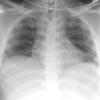

Nl Fat 1b

Date: 04/17/2005

Views: 4023